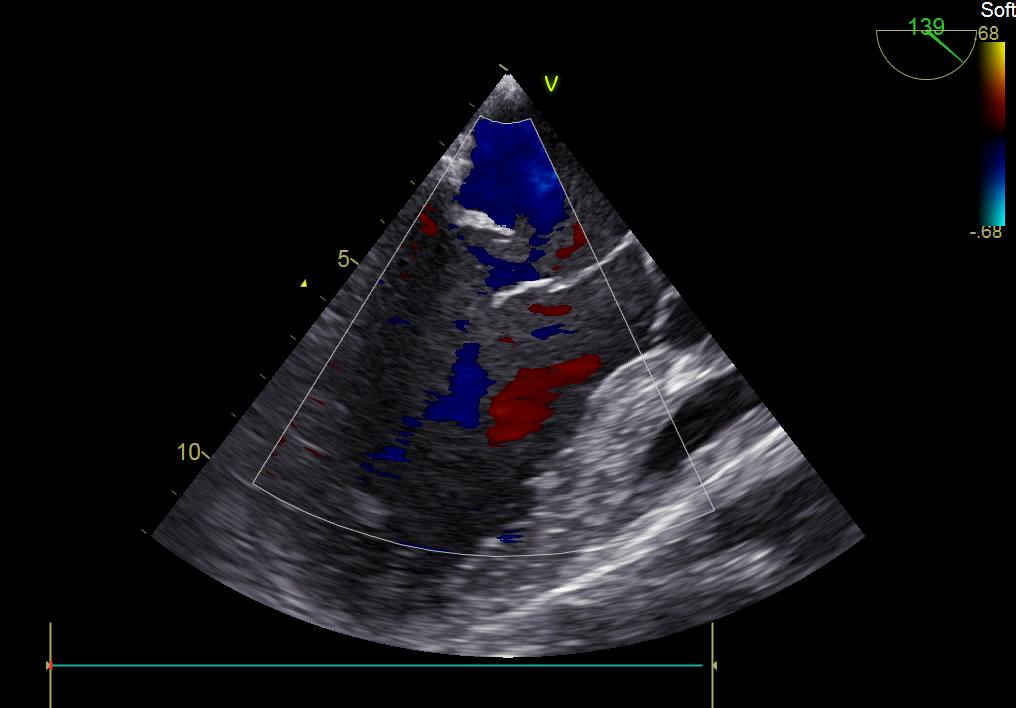

患者何某,42歲男性,因心功能不全入住我院心胸外科,心臟彩超提示二尖瓣后葉脫垂伴有重度返流及心臟擴大,在迅速糾正心衰后,手術(shù)便提上日程,心胸外科廖金文主任多次組織全科及兄弟科室討論,在二尖瓣置換及成形術(shù)上,最終決定采取二尖瓣成形術(shù)。為保證手術(shù)安全,討論圍手術(shù)期各個細節(jié),所謂細節(jié)決定成敗,因為術(shù)前的細致全面,加上術(shù)中的一絲不茍及術(shù)后的精細化管理,患者術(shù)后恢復(fù)順利,健康出院,復(fù)查心臟彩超未見二尖瓣返流。

術(shù)前彩超